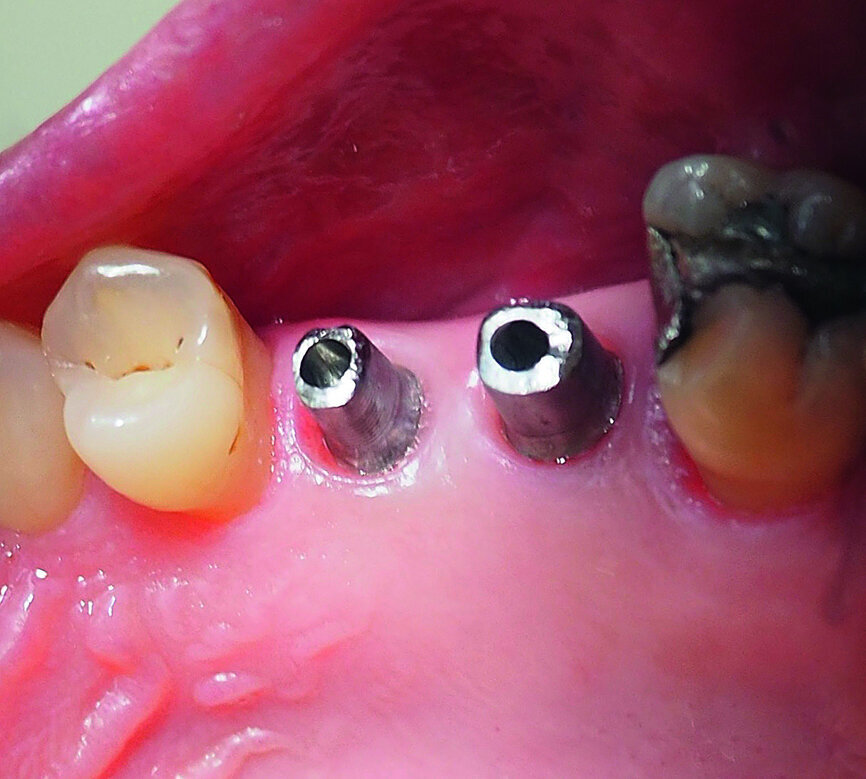

Fig. 1: The patient’s upper right first molar and second premolar had been missing for several years.

Fig. 20: Sulcus formers prior to fitting of the final restorations.

Fig. 21: The gingival tissue after removal of the sulcus formers.

Fig. 22: Custom-made Atlantis titanium abutments fitted to the implants.

The implants were restored four months after placement, with custom-made Dentsply Atlantis titanium abutments and Lava zirconia crowns (3M ESPE; Figs. 20–25).